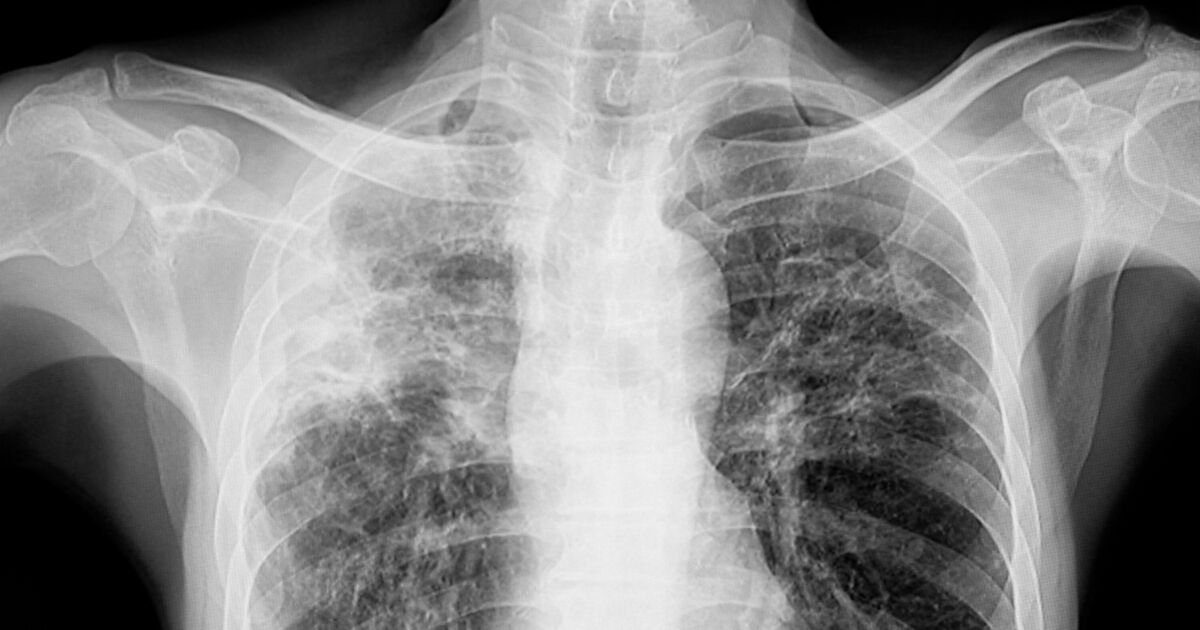

TB mainly affects the lungs but can also impact other parts of the body. It spreads through the air when an infected person coughs or sneezes. This means that close contact with someone who has TB increases the risk of infection.

Health experts warn that the rise in drug-resistant TB strains is alarming. This makes treatment more difficult and increases the potential for outbreaks. Recent statistics show that there are still thousands of new TB cases in the UK every year.